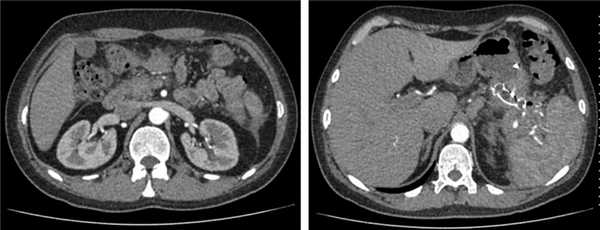

По данным контрольной КТ органов брюшной полости через 4 нед, в области головки ПЖ полость кисты отсутствует, в области хвоста псевдокиста ПЖ значительно «спалась» до внутреннего края нитинолового стента (рис. 6).

Рис. 6. Компьютерная томограмма органов брюшной полости с внутривенным усилением (после лечения).